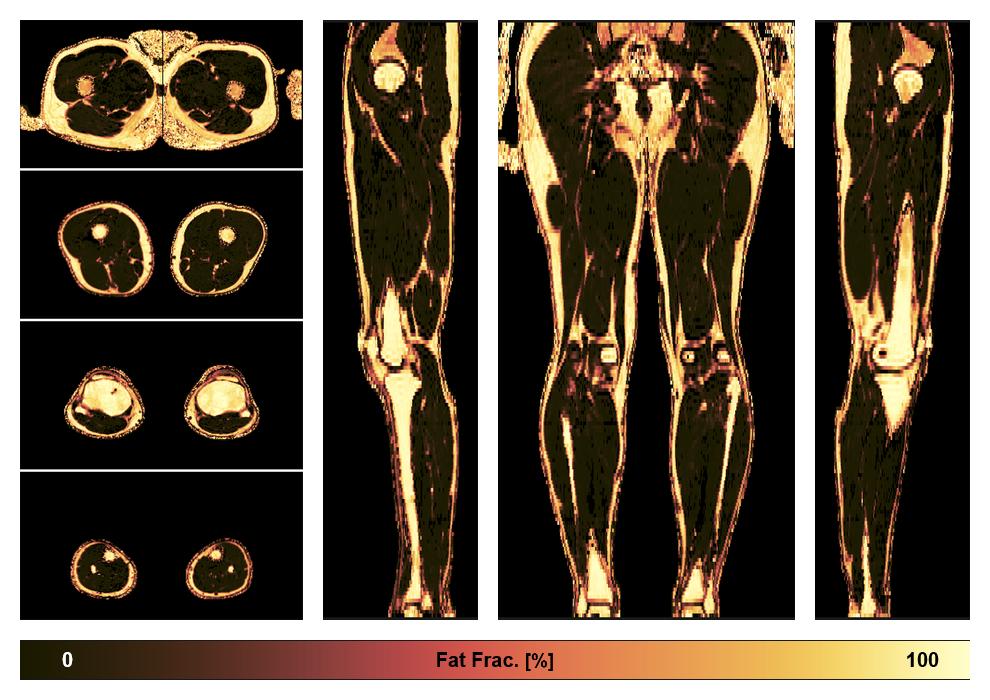

• Fat fraction

The fat fraction of the lower extremity obtained from the dixon reconstruction for muscle water fat quantification.